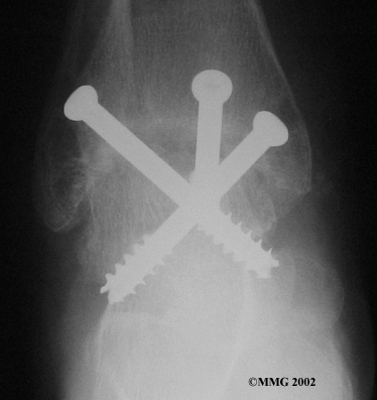

Ankle Fusion

When the ankle joint becomes so painful that it is difficult to walk, surgery may be suggested to fuse the ankle joint. An ankle fusion is sometimes also called an ankle arthrodesis. In this operation, the three bones that make up the ankle joint (the talus, the tibia, and the fibula) are allowed to grow together, or fuse, into one bone. Once this is done the ankle no longer is able to move, but with a successful fusion the pain is gone. Most people with a successful fusion of the ankle are able to walk without much trouble, and in some cases it is almost impossible to tell that the ankle is stiff. But it is very difficult to run because you lose the ability to push off with the toes. The foot can't bend down.

Most people will need some changes made to their shoes following an ankle fusion. Because the ankle no longer moves, it is difficult to roll over the top of the foot when you take a step. For this reason, shoes are usually fitted with a rocker sole. This allows the shoe to roll instead of the foot. A special heel is sometimes built on the shoe to absorb some of the shock.

The ankle fusion is a good operation, especially for a young, active person. It is usually the preferred option for post-traumatic arthritis of the ankle. Once the ankle is successfully fused it can last a lifetime, and no other operations are expected later unless there are problems. But there are complications associated with the ankle fusion, and not all ankle fusions are successful.

The biggest problem with the older artificial ankle designs is that they loosened after a relatively short time and began to cause pain. When using the newer artificial ankle designs, surgeons have tried to solve this problem by actually fusing the tibia and fibula together during the operation and placing screws across the two bones. This has dramatically increased the success rate for the artificial ankle replacements done today. Many surgeons are now beginning to use the artificial ankle for post-traumatic arthritis instead of doing a fusion. Patients are able to keep the motion in the ankle and avoid some of the problems associated with the ankle fusion.